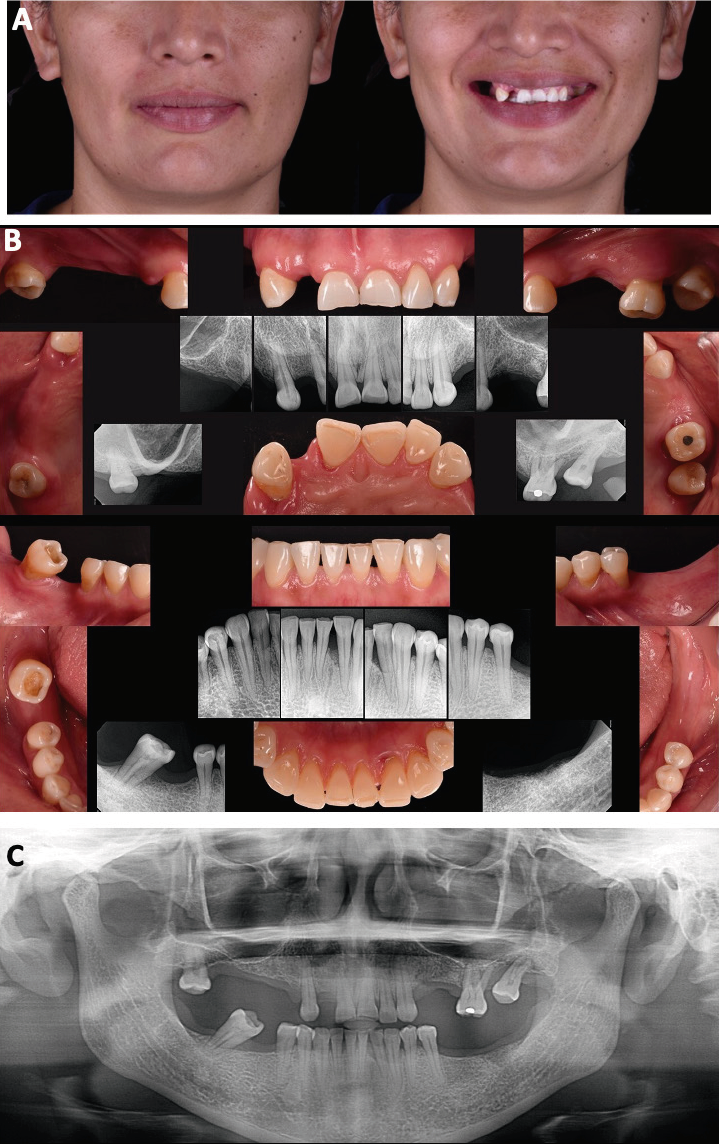

Al realizar el análisis extraoral de la paciente se observó que presentaba un biotipo facial dolicocefálico; la línea media facial muestra armonía, la línea interpupilar se encontró paralela con la línea intercomisural. La línea media facial se encontraba casi coincidente con la línea media dental, así como la línea interpupilar e incisal. Los tercios faciales eran simétricos, se encontraban dentro de los parámetros normales y equilibrados entre sí. El análisis de los parámetros estéticos (Tabla 1) se realizó en fotografías de perfil. En el análisis de sonrisa, la paciente presentó una dinámica labial media y amplia, en la cual el borde incisal se posicionaba sobre el labio inferior y hacía evidentes las múltiples ausencias dentales y los corredores bucales amplios (Figura 1. A).

Figura 1 Estudios iniciales. A. Fotografías extraorales de frente y sonrisa. B. Radiografías y fotografías de arcada superior y radiografías y fotografías de arcada inferior. C. Ortopantomografía.

Al análisis intraoral ambas arcadas presentaban forma cuadrada, procesos discontinuos y se apreció una banda ancha de encía queratinizada generalizada en todos los sextantes. En la arcada superior había ausencia de múltiples dientes, exposición radicular y malposición dental; se observó una pérdida de sustancia dental generalizada en bordes incisales, acentuándose en incisivos centrales, los cuales estaban extruidos. Presentaba caries oclusal y una restauración previa de amalgama en zona de molares (Figura 1. B). Radiográficamente se observó pérdida de soporte óseo en los molares izquierdos, ausencia de diversos dientes en el sector posterior, exposición radicular en premolares de ambos lados y malposición del molar; los incisivos mostraban una pérdida de sustancia dental en bordes incisales, así como triángulos negros interproximales. Adicionalmente se mostró un defecto óseo vertical entre los dientes 31 y 32, permeabilidad de los senos maxilares, éstos se encuentran desocupados; el proceso alveolar superior derecho se observa en contacto estrecho con el seno maxilar, y el trayecto del nervio dentario inferior (Figura 1. B-C).

En el análisis oclusal presentó una sobremordida horizontal de 5mm en máxima intercupidación (Figura 2. B) y de 8mm en relación céntrica (Figura 2. C), discrepancia entre máxima intercuspidación y relación céntrica de 3mm, sobremordida vertical de 3mm (Figura 2. C) y un espacio libre interoclusal de 5mm. El objetivo del tratamiento fue la rehabilitación oral completa mediante el análisis estético, radiográfico, encerado, mock-up e intervenciones quirúrgicas pre protésicas para acondicionar la cavidad bucal y recibir los implantes y las restauraciones finales.